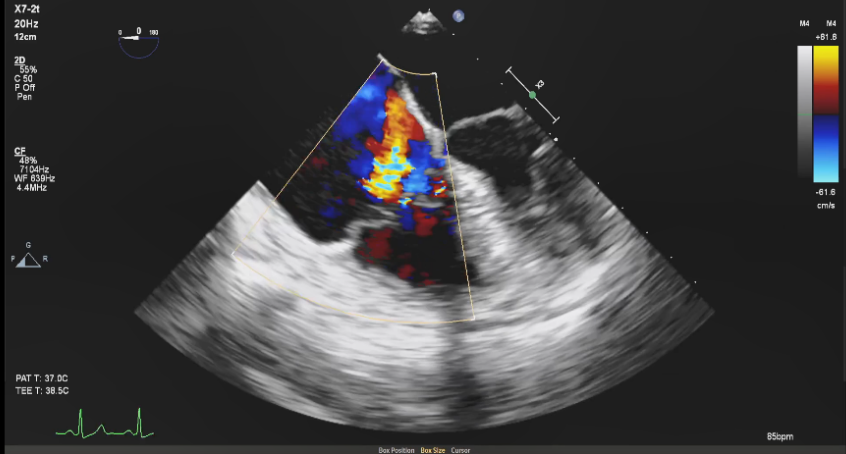

图1:术前超声提示极重度三尖瓣反流